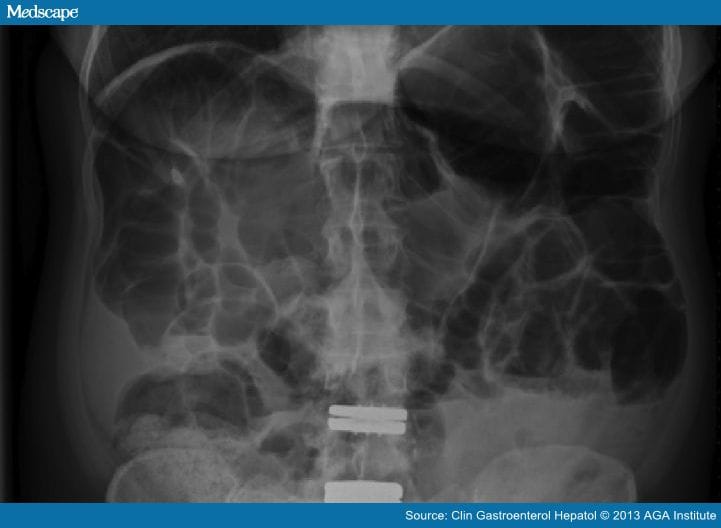

Bloating and abdominal distention are very common symptoms in patients with irritable bowel syndrome, functional dyspepsia, and constipation, but true aerophagia is very rare. In 2009, the first report in which the existence of a syndrome of excessive air swallowing in patients with symptoms of bloating and distention and signs of excessive intestinal air on abdominal radiographs was unambivalently shown was published in this journal.[73] By using impedance monitoring, it was observed that a group of patients with isolated excessive intestinal gas and symptoms related to this showed excessive air swallowing. Other symptoms besides bloating were flatulence, abdominal or epigastric pain, and constipation. Gastric belching is usually not the predominant symptom in these patients and supragastric belching is not observed at all in patients with aerophagia. In some patients with true aerophagia, episodes of air swallowing and symptoms can be distinguished followed by episodes without complaints. In such episodes patients report abdominal distention accompanied by pain and belching (Table 5). A differential diagnose with a mechanical ileus can be difficult and 30% of our patients have undergone a negative explorative laparotomy after presentation at the emergency room. In retrospect, the abdominal radiographs showed distended intestinal loops but no air-fluid levels and thus no evidence of obstruction (Figure 2). Laparotomy thus should be avoided in these patients.

Figure 2.

Abdominal radiograph of a patient with aerophagia showing a large volume of intestinal and colonic air; there are some signs of constipation as well but no air-fluid levels. Impedance monitoring showed massive air swallowing.